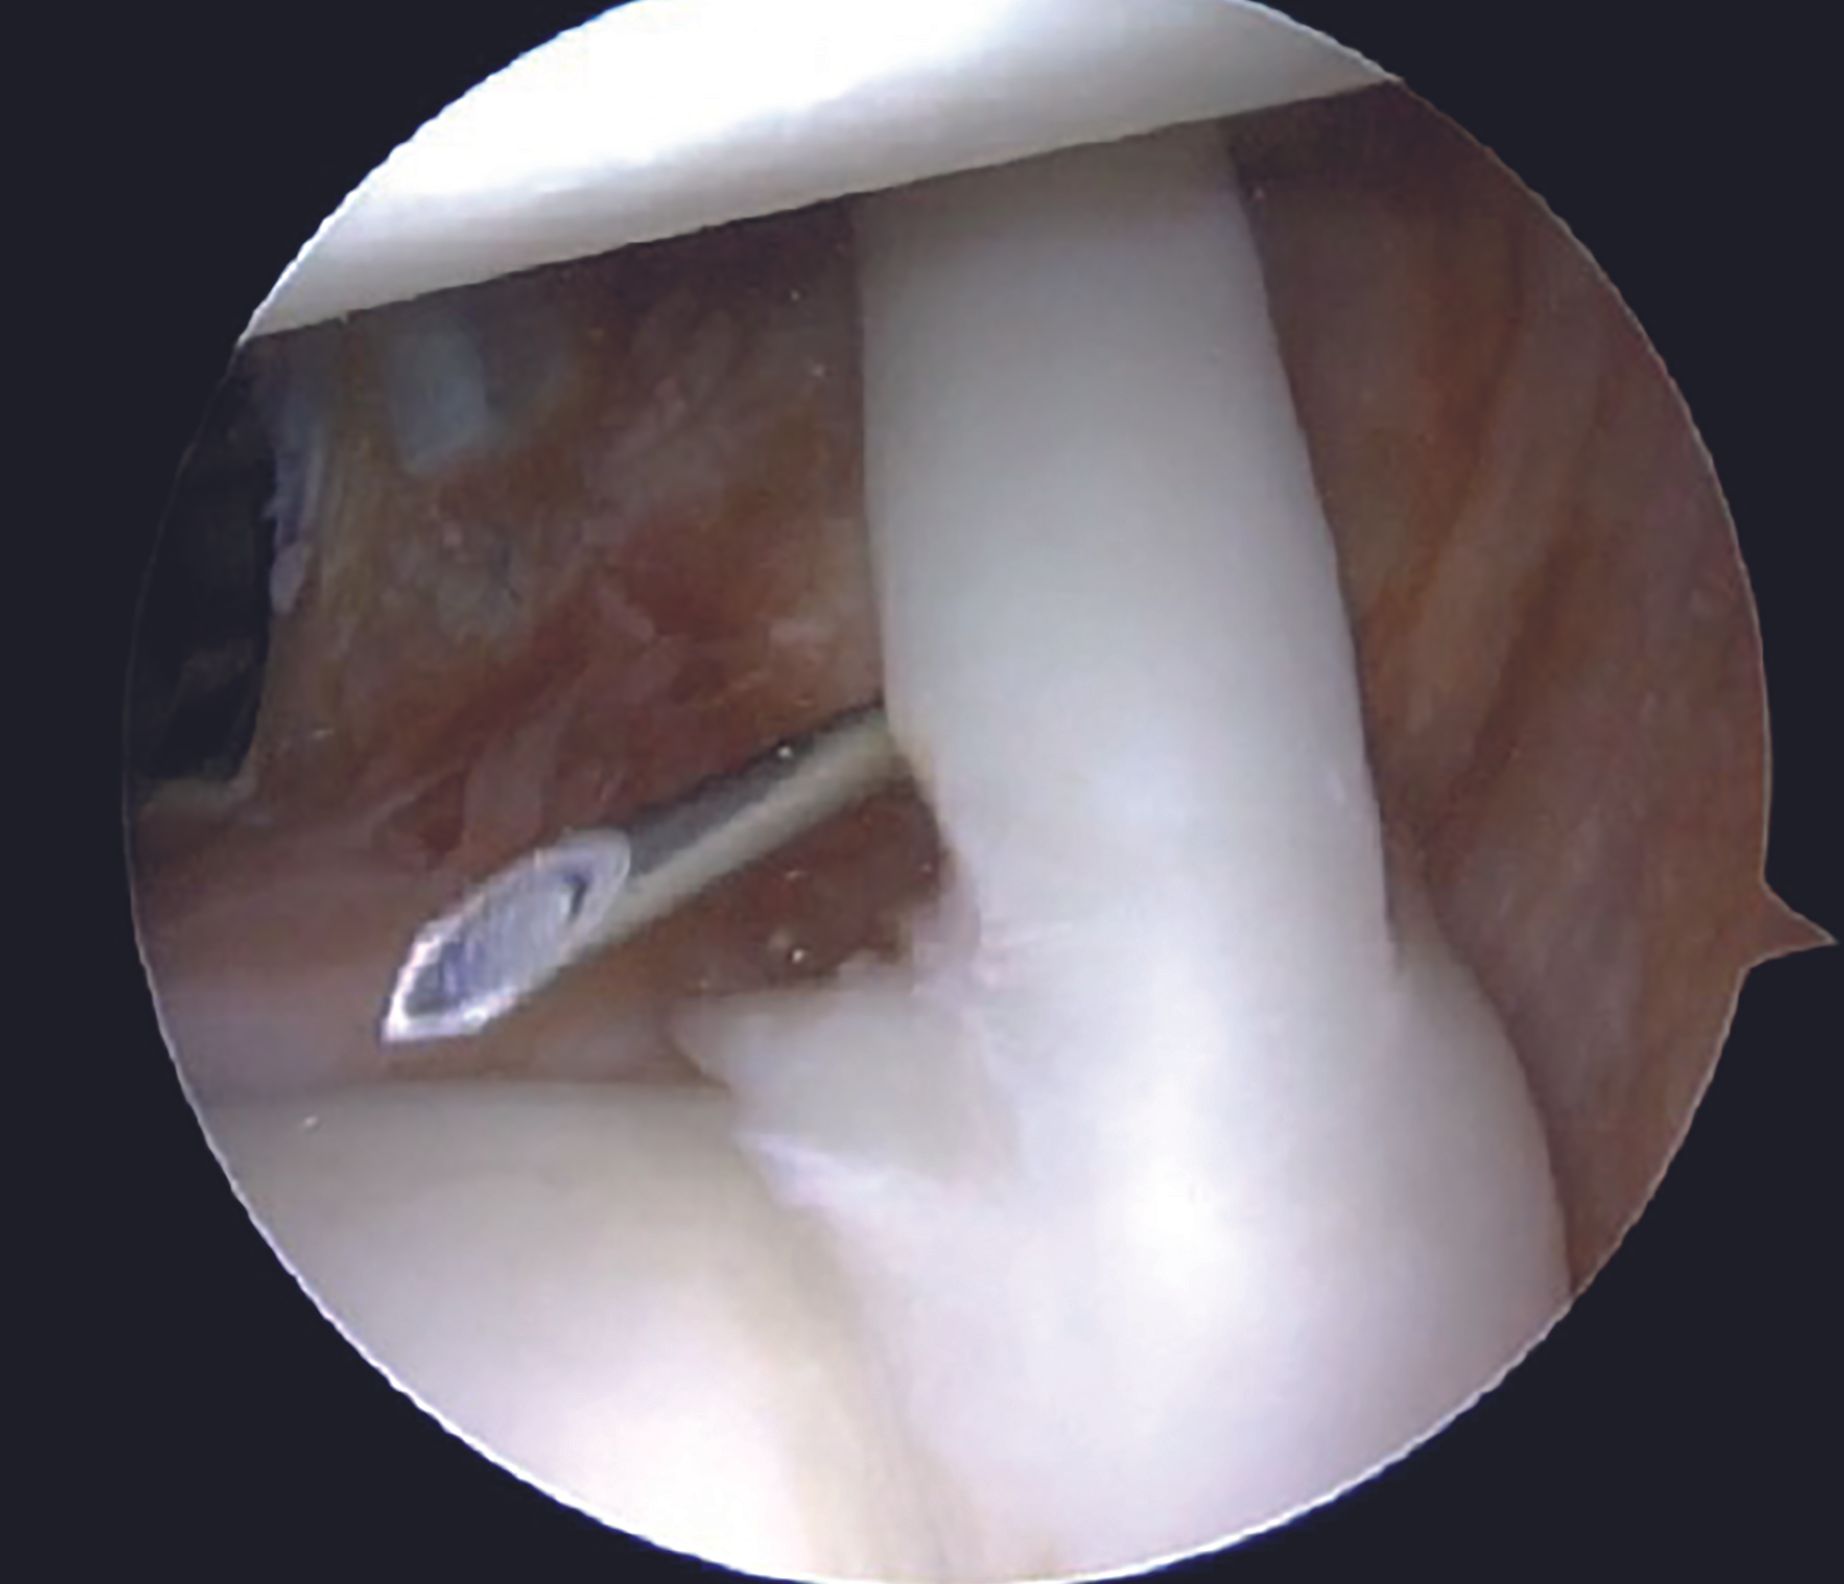

Adequate mobilization of the labral tissue from glenoid neck remains a crucial step for an effective Bankart repair. Adequacy of the labral mobilization is indicated by floating of the labral tissue at the level of articular surface of the glenoid. Care should be taken while liberating the labral tissue at 6 O'clock position in order to prevent an injury to the axillary nerve. Frayed tissue at the edge of the glenoid is cleared using a motorized 3.5mm arthroscopic shaver (Figure 7). Anterior glenoid bony surface is freshened with the help of a rasp in order to promote healing (Figure 8).

Anchor placement

For an isolated Bankart lesion, 3 anchors are usually sufficient. Our preferred choice for the anchor is 1.8mm all-suture anchor as the affected patients are young and thus possess a good quality of the subchondral bone. Advantages of all-suture anchors such as absence of metal implants, no interference with post-operative imaging, easier revision, are well known. Anchor with a tape is preferable to avoid cut-through through the labral tissue. Inferior most anchor is placed first at 5-5.30 O'clock position after drilling a hole using a sleeve through the AI portal (Figure 9). After tapping the anchor in, it is important to pull the tapes so that the anchor bunches up beneath the subchondral bone (Figure 10). Free passage of the tapes is ensured.